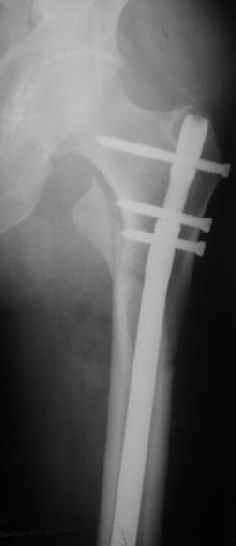

Женя, эта картинка показывает не оптимальное лечение вертельных переломов в моем представлении, а особенности дизайна упомяутого фиксатора.

В частности, его возможности при фиксации переломов проксимального отдела бедра - в сравнении с другими, имеюшими лишь по одному статическому и динамическому отверстию и с кондуктором для введения 2 винтов.

Это было года 2,5 назад, мы тогда еще уточняли возможности шинирования с угловой стабильностью гвоздем с поперечным расположением винтов при переломах проксимального отдела бедра. Пациенту не пришлось приобретать намного более дорогой рекон или проксимальный гвоздь. В приложении еще несколько примеров применения того гвоздя при высоких переломах бедра, в том числе с более латеральной точкой входа. Гвоздь изгибаем для этого.